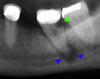

Apical radiolucency with sinus tract marker leading to apex – diagnosis?

• Periodontitis periapicalis chronica cum fistula

• (chronic apical periodontitis with fistula).

• Treatment: RCT or extraction

* Periodontitis periapicalis chronica cum fistula * (Chronic apical periodontitis with fistula) → Gutta-percha point tracing to apex